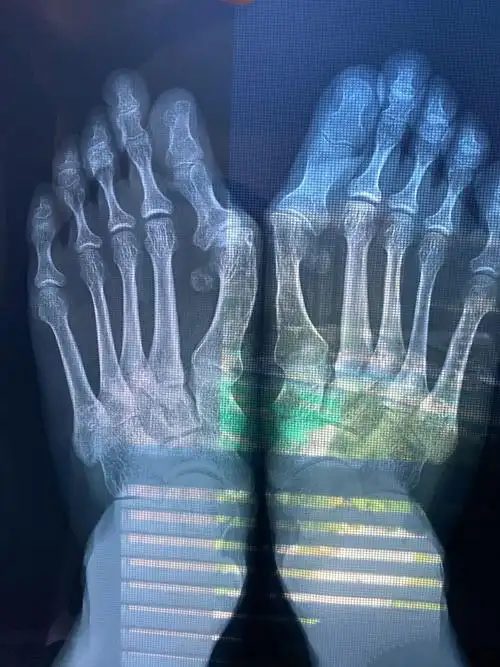

负重x线片观察:第一二跖骨间夹角增大明显,第二跖趾关节半脱位.

36岁双足拇外翻畸形矫正手术一例

x光片更直观了解大脚骨 如果单纯去掉凸起能否有效矫正拇外翻呢?